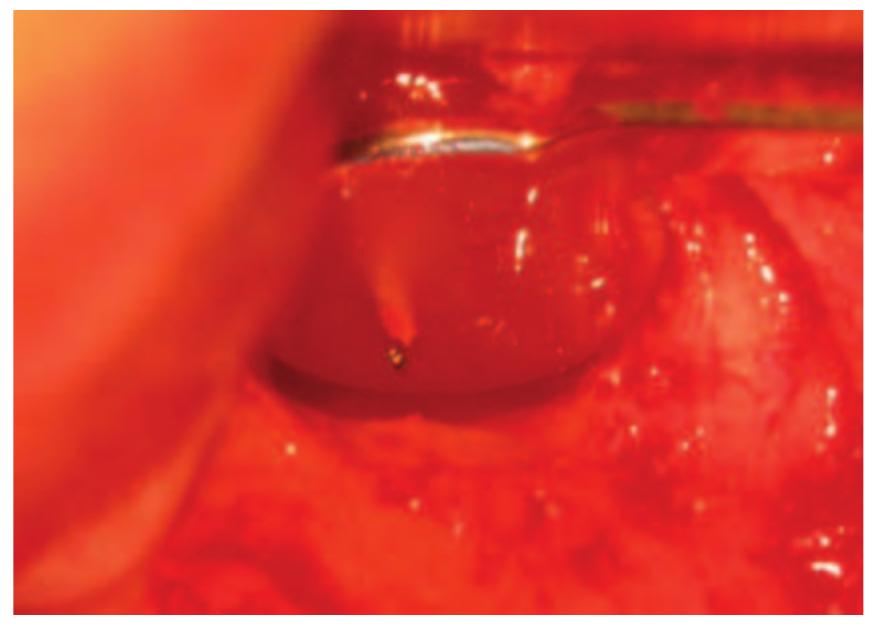

- In the majority of cases, root end surgery would not be carried out unless the root canal had been thoroughly cleaned prior to treatment.